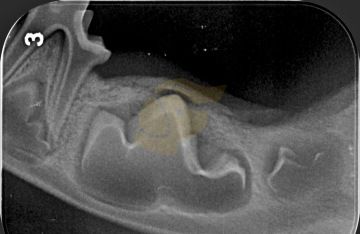

Postižení temporomandibulárního kloubu

podrobné vyšetření dutiny ústní a orofaciální oblasti, zhotovení rentgenových snímků, fotodokumentace, pacienty často posíláme i na CT / MRI dané oblasti, zhodnocení a sestavení terapeutického plánu, terapie dle výsledků, edukace majitele